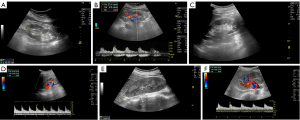

Initially, grayscale US imaging was performed. The kidney was visualized in a longitudinal section with the patient in a prone position, and the bipolar length of the kidney, defined as the largest distance between the upper and lower poles, was measured. Following this, color Doppler US was employed to assess the main trunk and branches of the renal arteries. The interlobar artery was identified using color-flow imaging, and the blood flow profile in the artery was monitored through spectral analysis. This method provided the best Doppler signal for assessing the quantity of flow and ensuring the correct angle (14,18).

For each patient, blood flow parameters were measured in the middle interlobar arteries of the kidney. These parameters included the minimum blood flow velocity (Vmin), maximum blood flow velocity (Vmax), and RI, which was calculated as follows: RI = (Vmax – Vmin) / Vmax. Measurements were taken only when at least three consecutive similar waveforms were observed. The renal artery waveform was captured with an angle of 60 degrees or less. The US imaging interpretations were determined through consensus by three radiologists (S.P.C., Z.Z., and M.G.; Z.Z. and M.G. had 10 years of experience in conventional US each). All three radiologists were blinded to the clinical diagnostic results at the time of the interpretation of the US imaging.